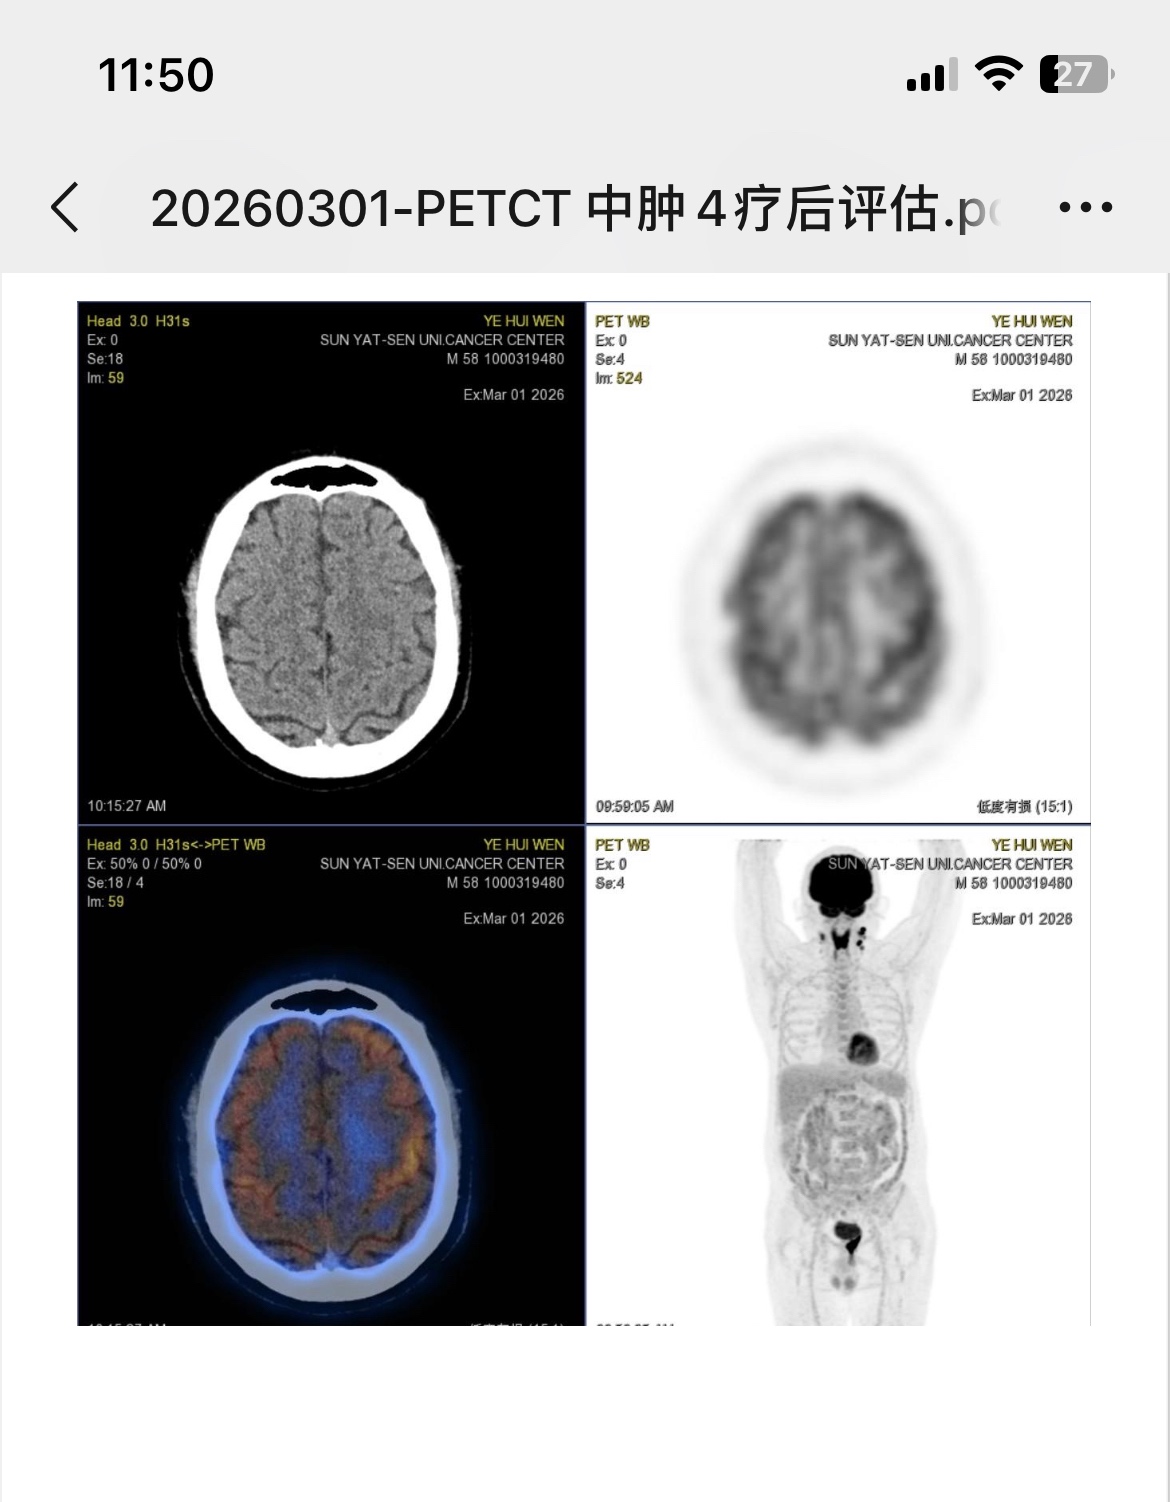

谢谢大神,如何判断是否局限期?看4疗的pet主要集中在颈部。但初治之前医生说是三期。

化疗前和4疗的pet

2疗后评估